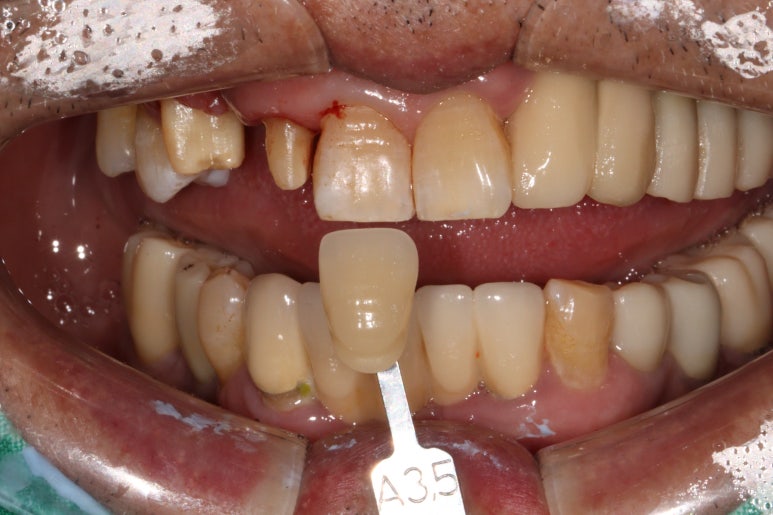

이를 제거하고 앞니 브릿지를 제작하기 위해 치아 삭제를 시행하였습니다.

shade guide를 사용하여 치아의 색상을 측정하였습니다.

A3.5를 적용하니 조금 어두우나 치경부와는 비슷한 색을 내네요.

치아가 다양한 색상을 갖고 계시기 때문에 최대한 자기 치아를 모방하기 위해 꼼꼼하게 치아색상을 기록합니다.

앞니 지르코니아 브릿지 제작을 위해